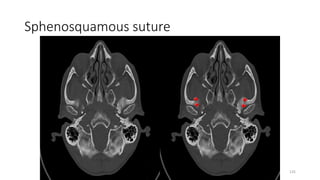

Sphenosquamous suture

SPHENO SQUAMOUS SUTURE